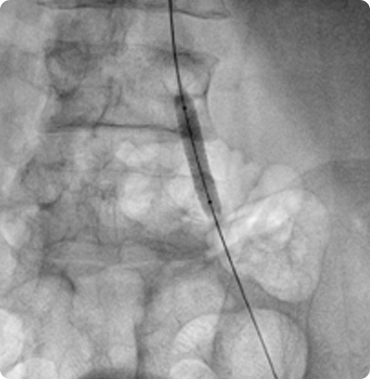

Together with a team of trained staff, his goal is to provide top care so that patients can achieve and maintain a healthy heart. He has done hundreds of angiographies and angioplasties...